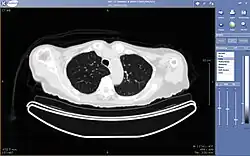

Typically a PACS consists of a multitude of devices. The first step in typical PACS systems is the modality. Modalities are typically computed tomography (CT), ultrasound, nuclear medicine, positron emission tomography (PET), and magnetic resonance imaging (MRI). Depending on the facility's workflow most modalities send to a quality assurance (QA) workstation, sometimes called a PACS gateway. The QA workstation is a checkpoint to make sure patient demographics are correct as well as other important attributes of a study. If the study information is correct the images are passed to the archive for storage. The central storage device (archive) stores images and in some cases reports, measurements and other information that resides with the images. The next step in the PACS workflow is the reading workstations. The reading workstation is where the radiologist reviews the patient's study and formulates their diagnosis. Normally tied to the reading workstation is a reporting package that assists the radiologist with dictating the final report. Reporting software is optional and there are various ways in which doctors prefer to dictate their report. Ancillary to the workflow mentioned, there is normally CD/DVD authoring software used to burn patient studies for distribution to patients or referring physicians. The diagram above shows a typical workflow in most imaging centers and hospitals. Note that this section does not cover integration to a Radiology Information System, Hospital Information System and other such front-end system that relates to the PACS workflow.

More and more PACS include web-based interfaces to utilize the internet or a wide area network (WAN) as their means of communication, usually via VPN (Virtual Private Network) or SSL (Secure Sockets Layer). The clients side software may use ActiveX, JavaScript and/or a Java Applet. More robust PACS clients are full applications which can utilize the full resources of the computer they are executing on and are unaffected by the frequent unattended Web Browser and Java updates. As the need for distribution of images and reports becomes more widespread there is a push for PACS systems to support DICOM part 18 of the DICOM standard. Web Access to DICOM Objects (WADO) creates the necessary standard to expose images and reports over the web through truly portable medium. Without stepping outside the focus of the PACS architecture, WADO becomes the solution to cross platform capability and can increase the distribution of images and reports to referring physicians and patients.